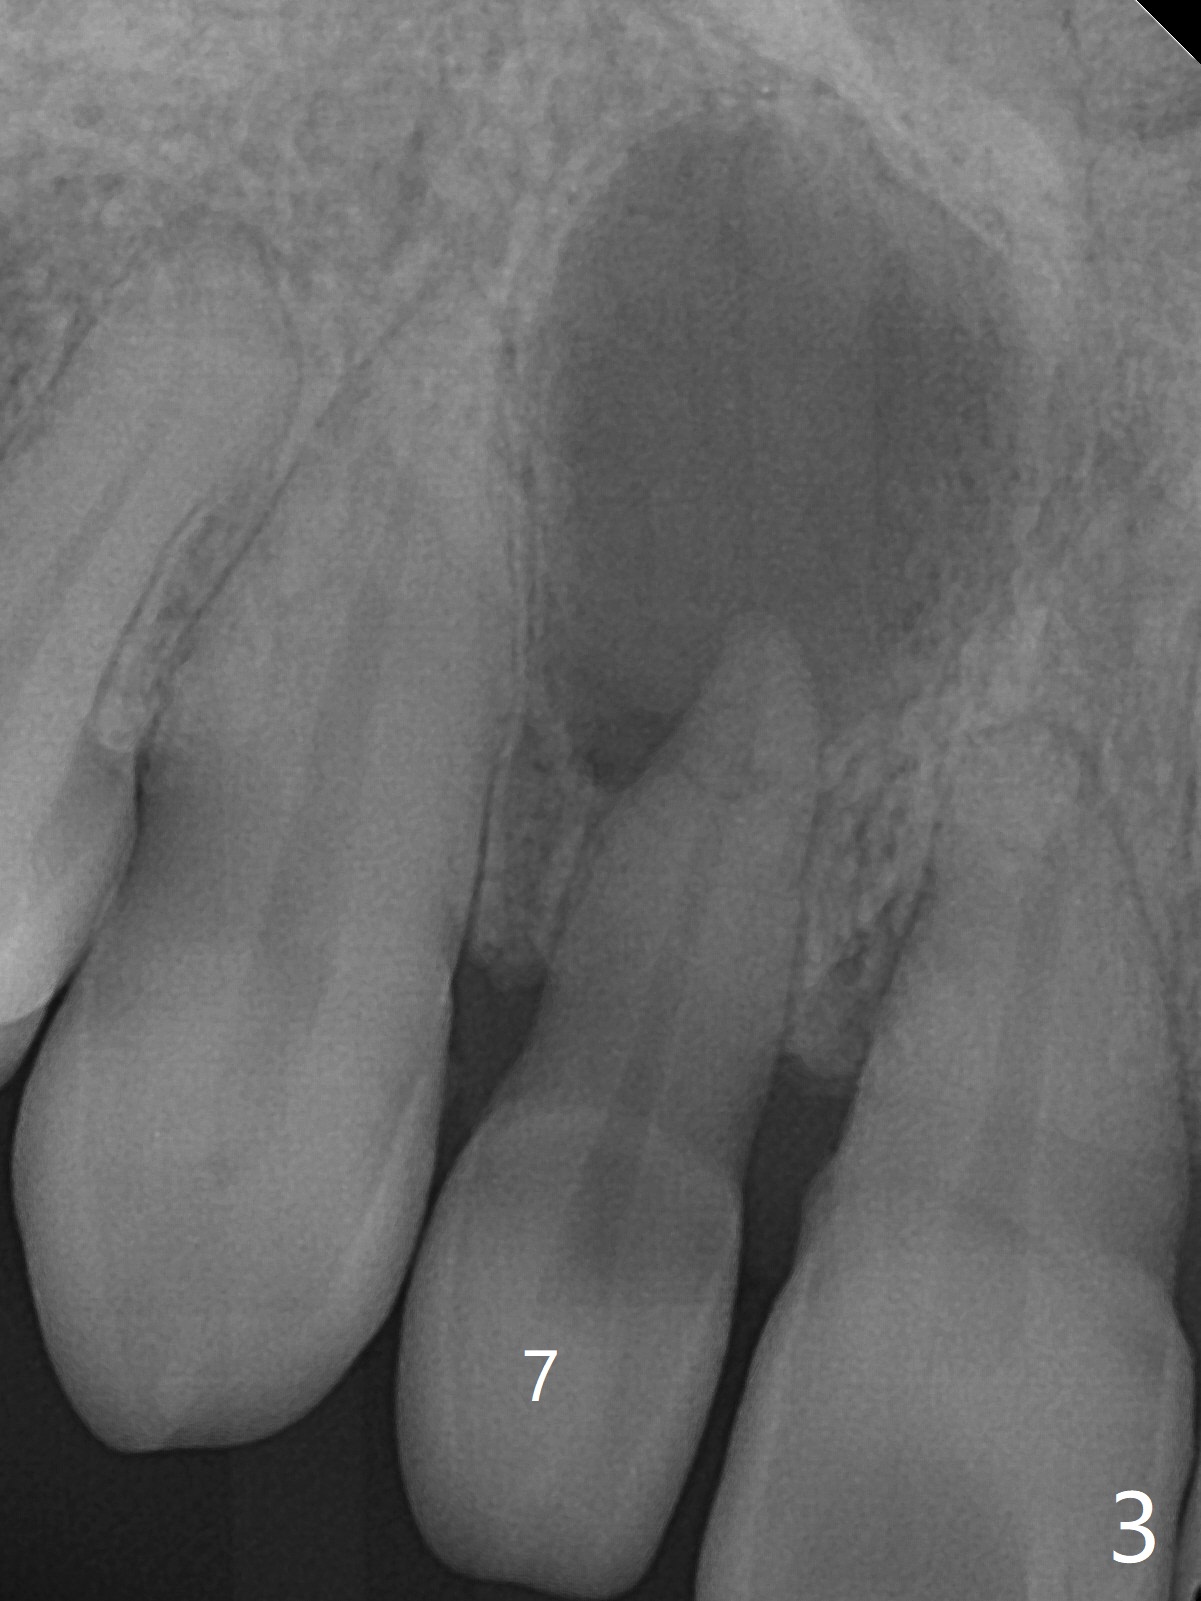

A 45-year-old woman presented to office for new patient examination. The latter reveals discoloration (Fig.1 necrosis on pulpal test; * labial concavity), microdontia with possible root canal malformation (Fig.2: M) and large inverted pear-shaped cyst (Fig.3) of the tooth #7. Guarded prognosis will be emphasized prior to treatment.